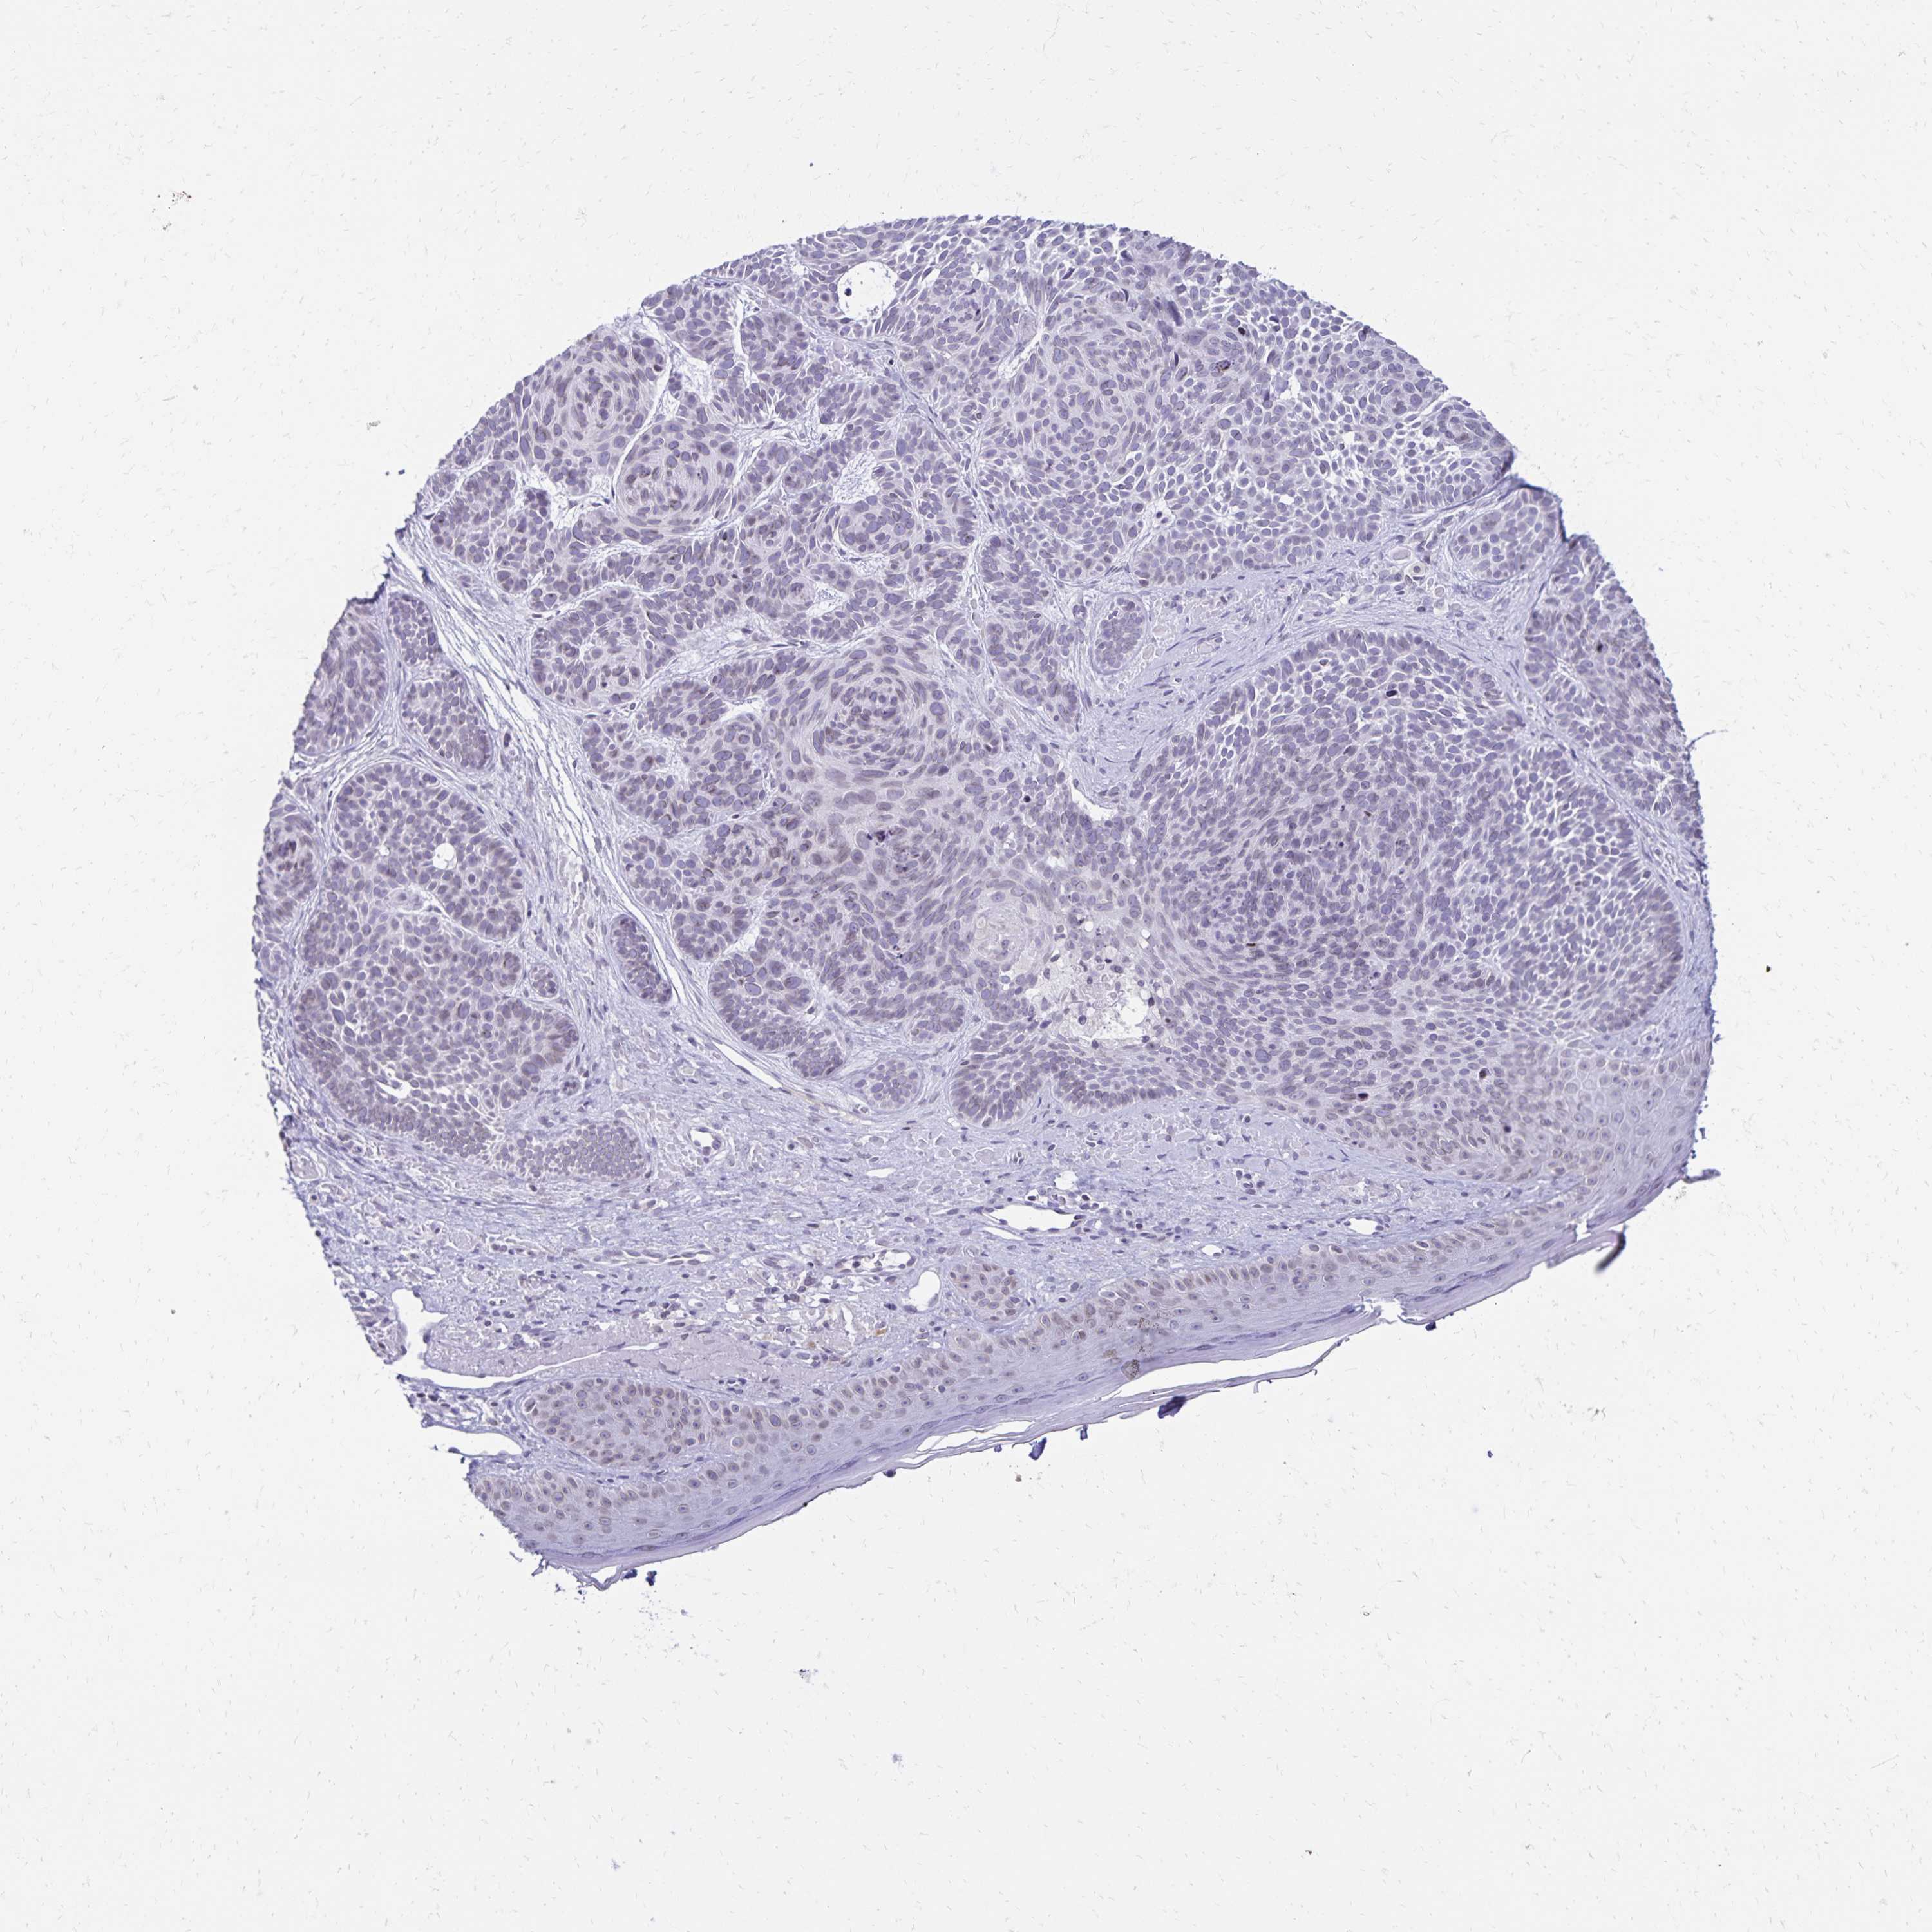

CANCER SKIN CANCER Show tissue menu

Basal cell and squamous cell cancer

SKIN CANCER - Protein expressioni

A mouse-over function shows sample information and annotation data. Click on an image to view it in a full screen mode. Samples can be filtered based on level of antibody staining by selecting one or several of the following categories: high, medium, low and not detected. The assay and annotation is described here.

Each image is clickable and will lead to virtual microscopy that enables deeper exploration of all samples and also displays staining intensity scores, fraction scores and subcellular localization as well as patient and tissue information for each sample.

Antibody HPA062453

Staining

High

Strong

Quantity

Location

Basal cell carcinoma